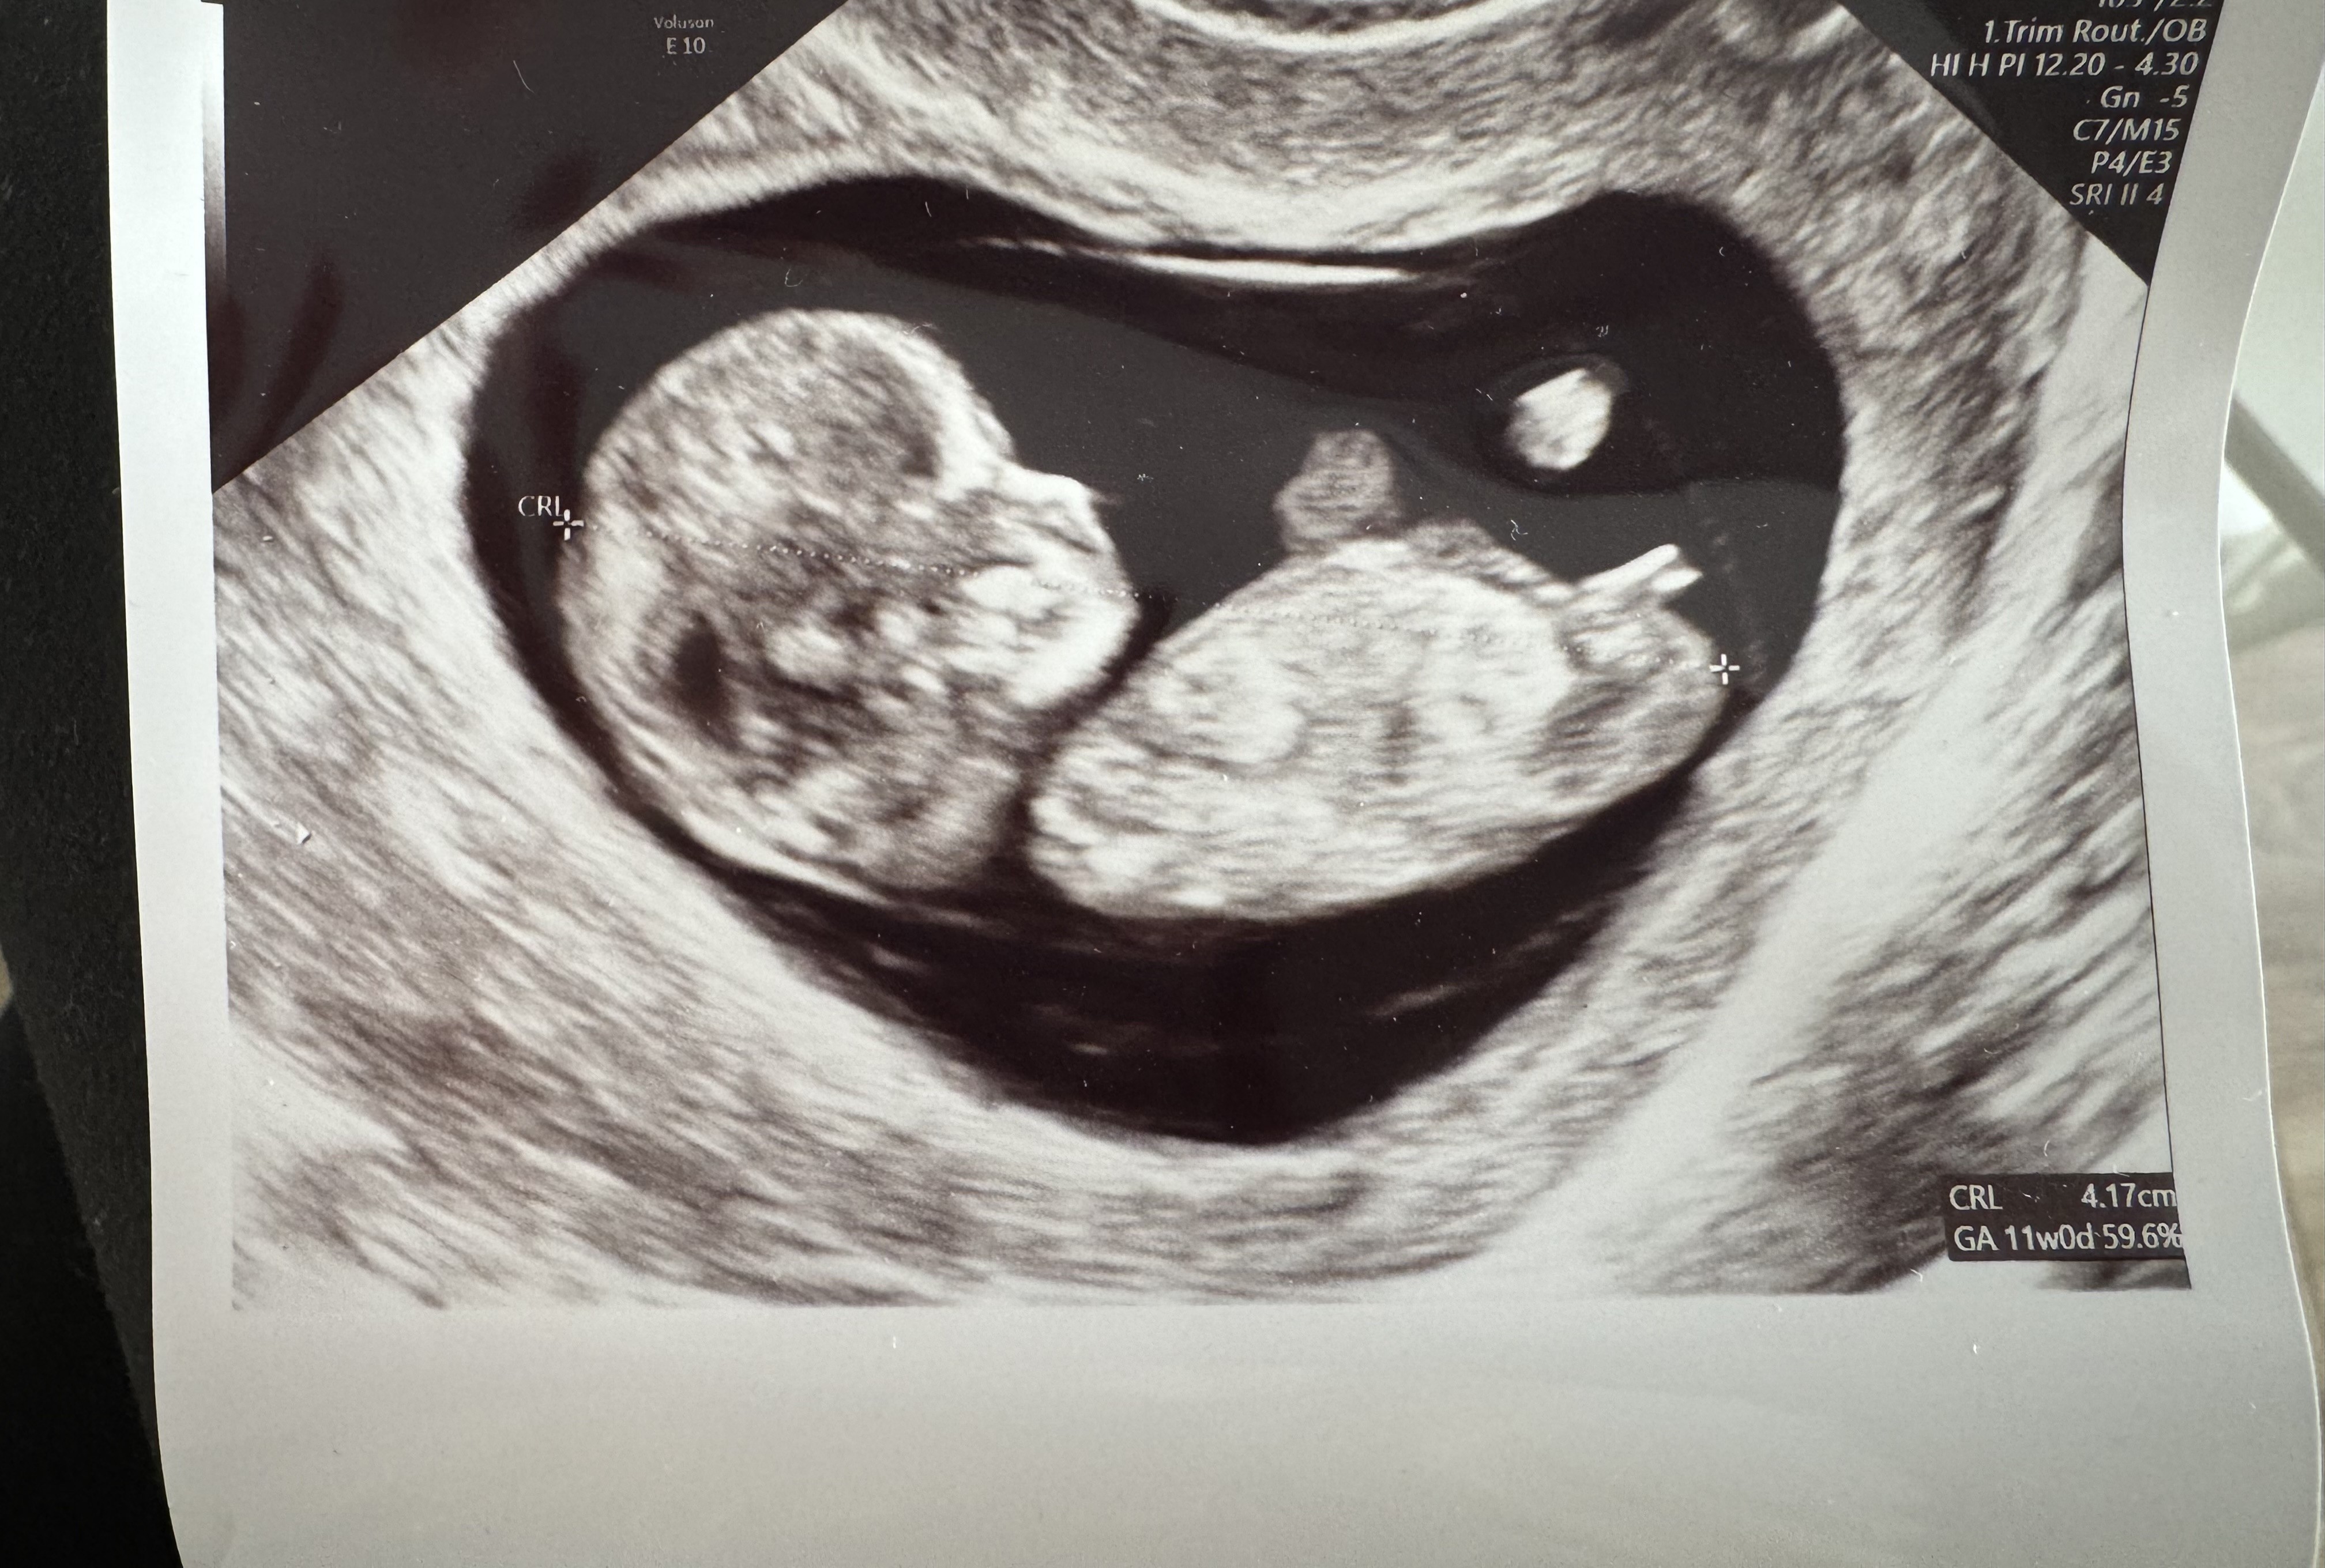

Hej dziewczyny, czy widzicie coś na tym zdjęciu z mojego USG. 18tc i Pani Doktor mówi że chłopak ale ja mam głęboka nadzieję na dziewczynkę, pomóżcie 😀